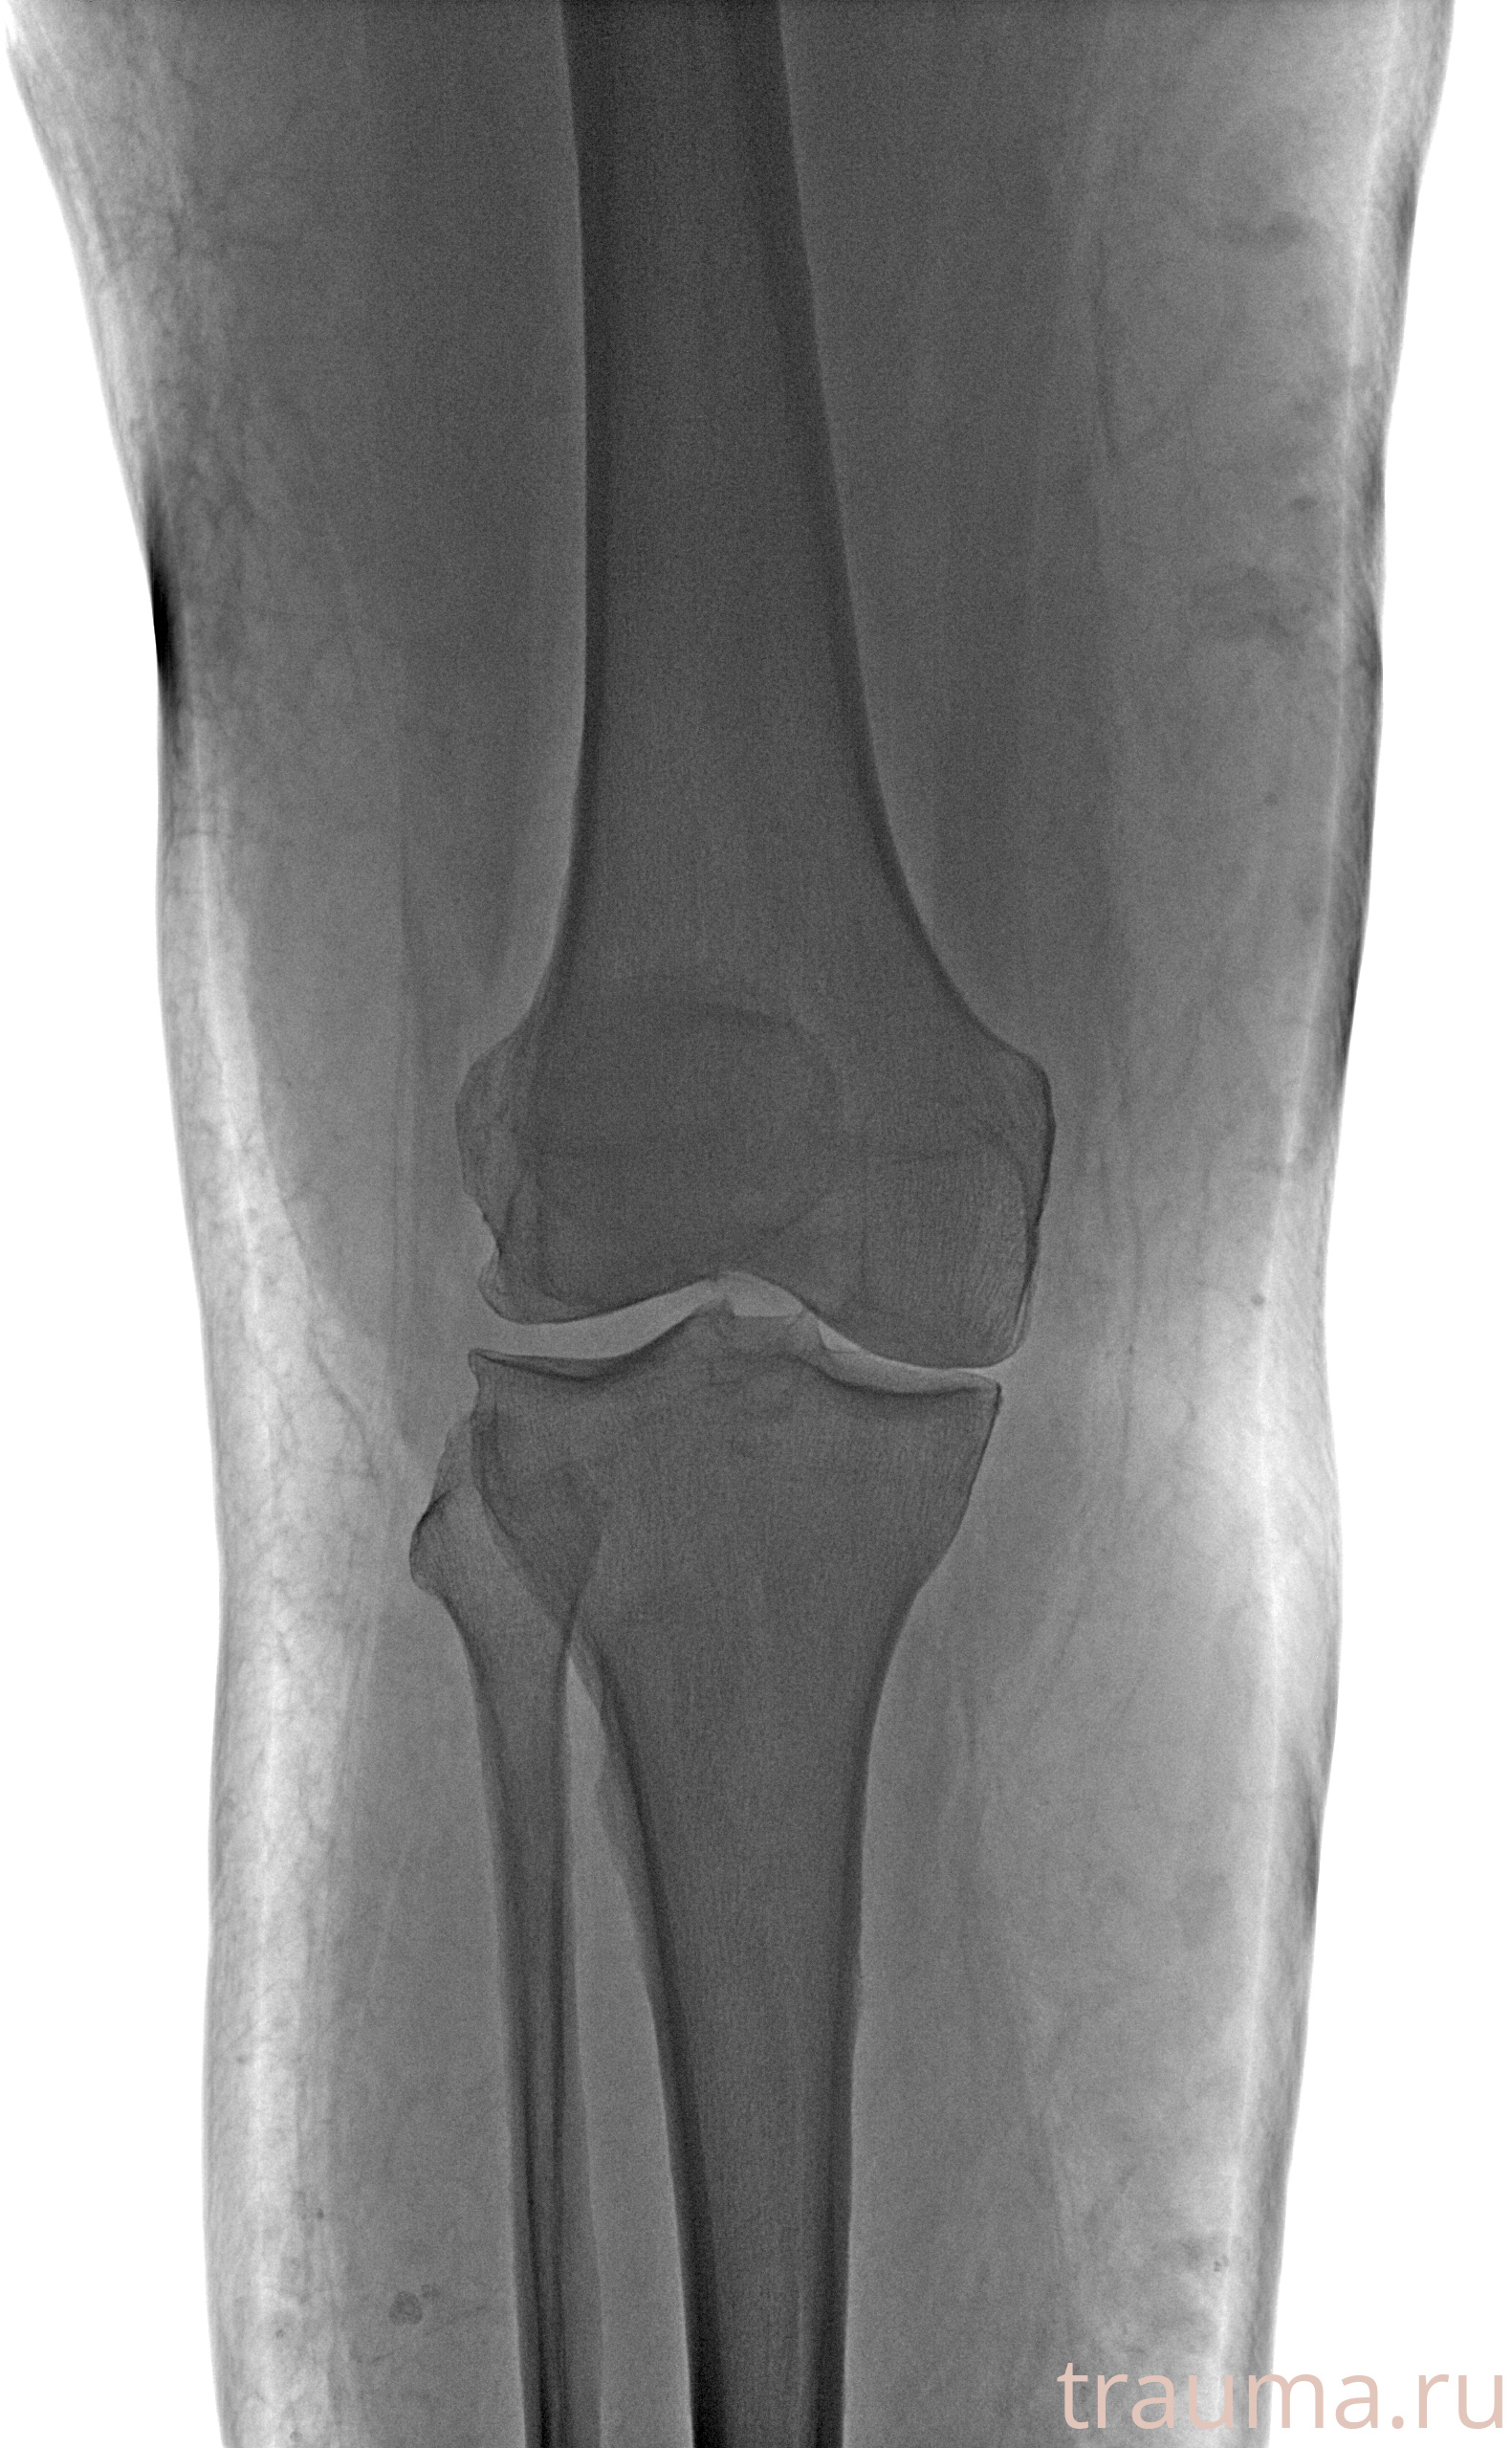

Рентгенограммы

Рентген на дому: по вашему адресу приезжает врач-рентгенолог, травматолог-ортопед с мобильным рентгеновским аппаратом, проводит диагностику травмы или заболевания, делает необходимые рентгенограммы, дает рекомендации по дальнейшему лечению. Получить качественные снимки в домашних условиях возможно благодаря уникальной методике, разработанной МосРентген Центром для института  Склифосовского